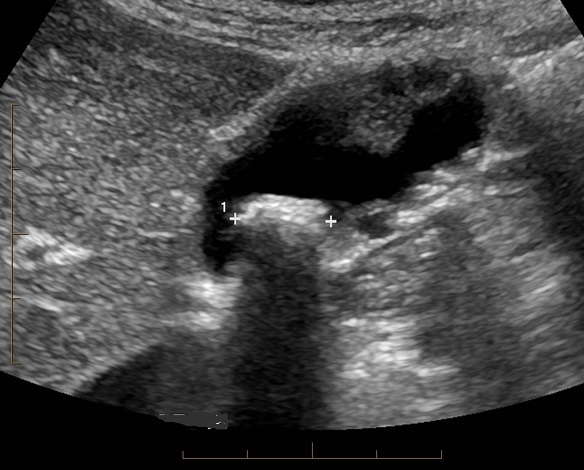

Aspect de epaississement a

bord irregulie de la vesicule biliaire avec image de

mass isoechogene intraluminal vesiculaire

. Image de grand calcul avec zone d'ombre

posterieure est en vue tres nette |